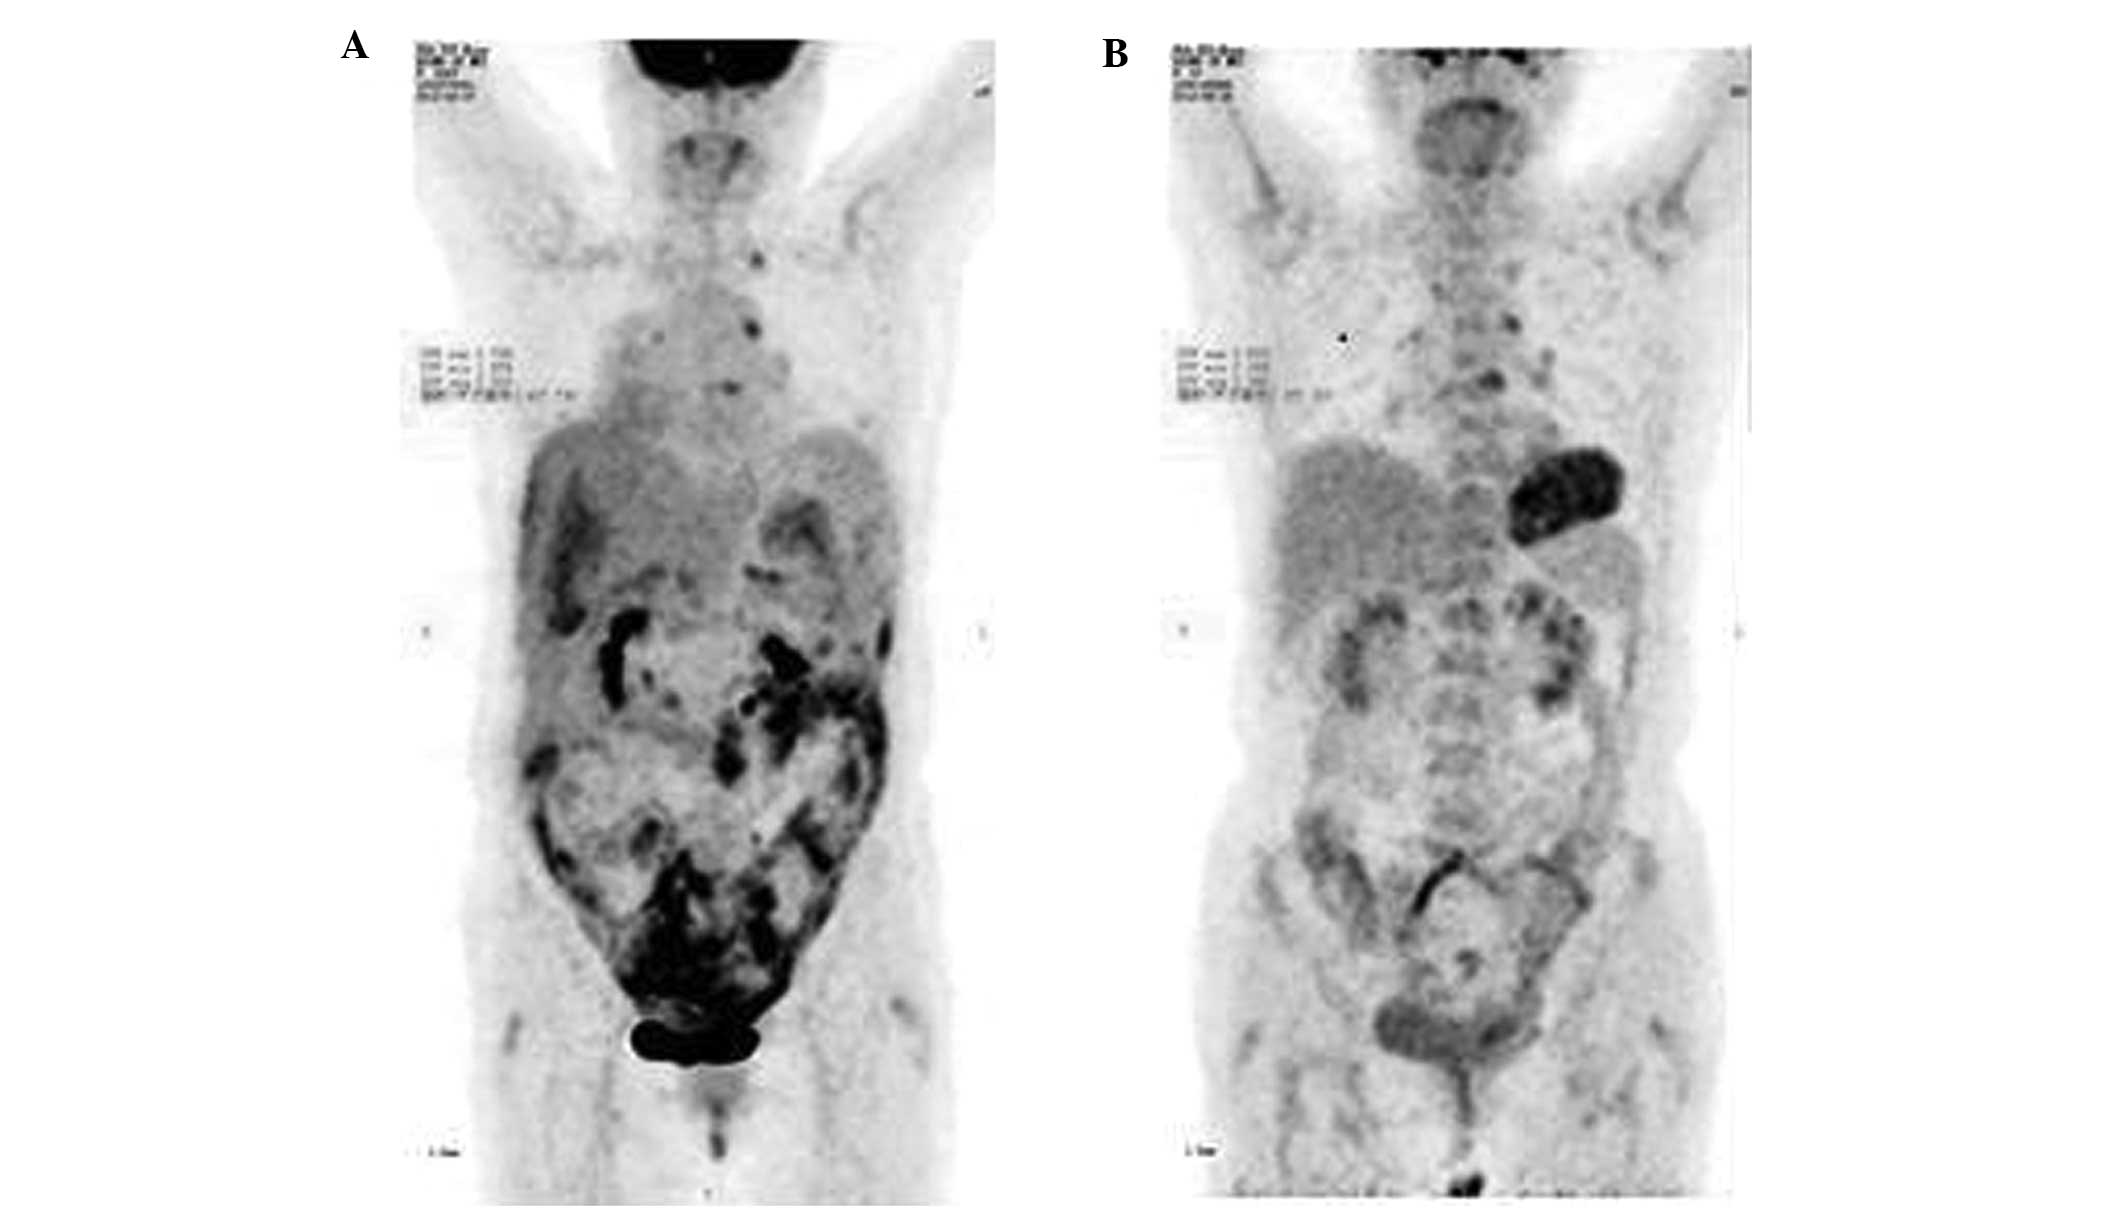

Imaging Techniques for the Diagnosis of Ovarian Cancers π